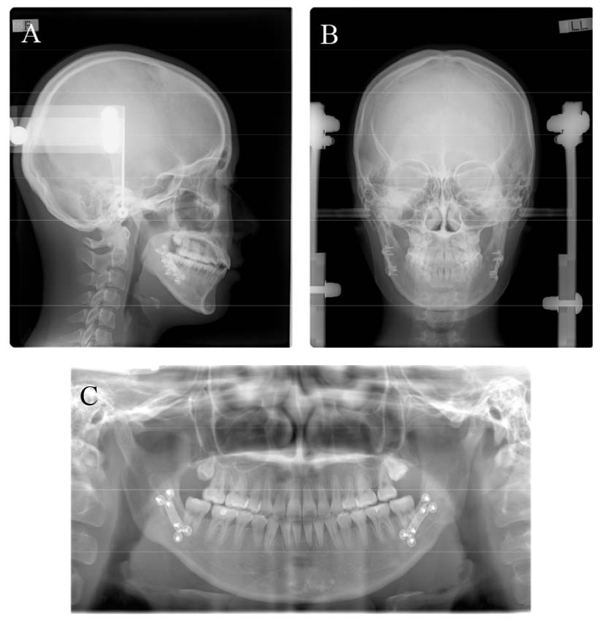

2.5. Treatment Results

The post-treatment records showed that the procedures resolved the occlusal cant and mandibular asymmetrical setback, improving the facial asymmetry (Fig. 5). The dental midlines were coincident with the facial midline, and proper class I canine relationships on both sides were achieved. The soft-tissue menton deviation was improved from 12.0 mm to 2 mm toward the left of the facial midline (Fig. 6). Panoramic radiography showed acceptable root paralleling without root resorption (Fig. 7). Cephalometric analysis (Fig. 7a and Table 1) and superimposition (Fig. 8) showed that a skeletal class I jaw relationship had been maintained (ANB angle, 5.0°), although the SNB angle was slightly decreased from 78.6° to 76.8° as a result of mandibular asymmetrical setback. The mandibular plane angle was increased slightly from 35.0° to 35.8° (FMA). The mandibular incisors were slightly proclinated from 56.2° to 53.6° (FMIA), and the maxillary incisors were slightly retroclinated from 113.6° to 111.6° (U1-FH).

The intrusion of the maxillary right dentition (N-side: U3-H 0.4 mm canine intrusion, U6MB 1 mm molar intrusion) and extrusion of the left dentition (D-side: U3-H 0.6 mm canine extrusion, U6MB 2.1 mm molar extrusion) resolved occlusal plane canting, contributing to facial asymmetry. Significant improvements were also seen in coronal ramus angle (N-side 78.0°, D-side 80.9°) and ramus position (Rma-H: N-side 55.9 mm, D-side 54.5 mm) after orthognathic surgery with BSSO.